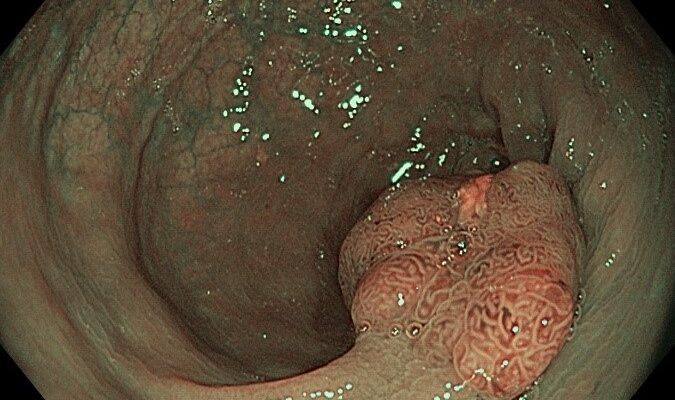

Rezecția polipilor colonici, denumită polipectomie, se realizează cel mai frecvent endoscopic, atunci când pacientul efectuează colonoscopia și sunt depistate aceste leziuni premaligne. În funcție de numărul, dimensiunea și rezultatul histopatologic ale polipilor rezecați sunt enunțate recomandările de monitorizare colonoscopică a...